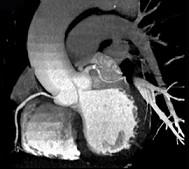

上面一组图像考虑为 ( )A、左前降支钙化B、左旋支钙化C、正常的左前降支D、右侧冠状动脉钙化E、正常的右侧冠状动脉

问题 上面一组图像考虑为 ( )

选项 A、左前降支钙化 B、左旋支钙化 C、正常的左前降支 D、右侧冠状动脉钙化 E、正常的右侧冠状动脉

答案 A